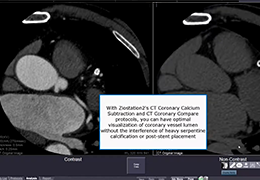

Designed mainly for CT and MR DICOM modalities.

Performs 3D reconstruction and volume rendering.

Window/level (brightness and contrast) presets.

Side-by-side comparative assessment for pre- and post-operative scans.